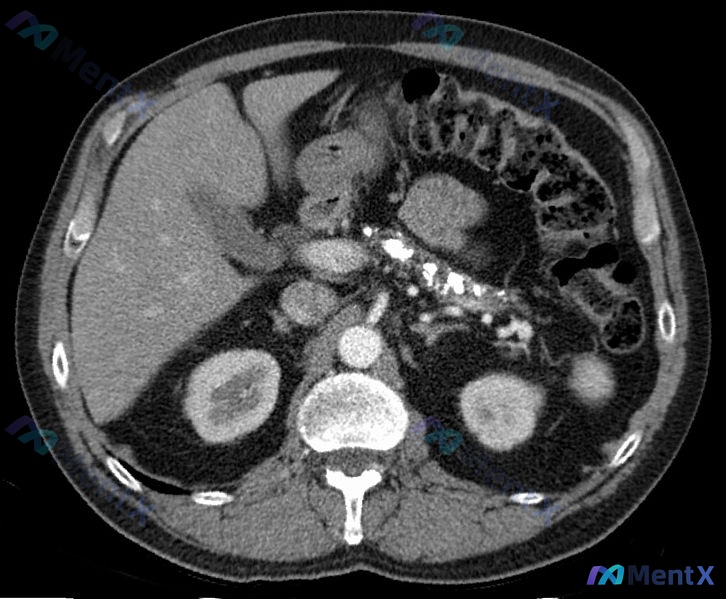

今天看到一个很有意思的影像分析场景,整理一下思路和大家分享。 --- 先看“影像事实”(基于这份单帧CT软组织窗横断面) 影像报告里的客观描述非常明确: 1. 脾脏:位于左侧,形态、大小及密度未见异常。 2. 其他实质脏器:肝右叶、胰头/部分胰体、双肾,实质密度均均匀,未见明确局灶性低/高密度占位,...